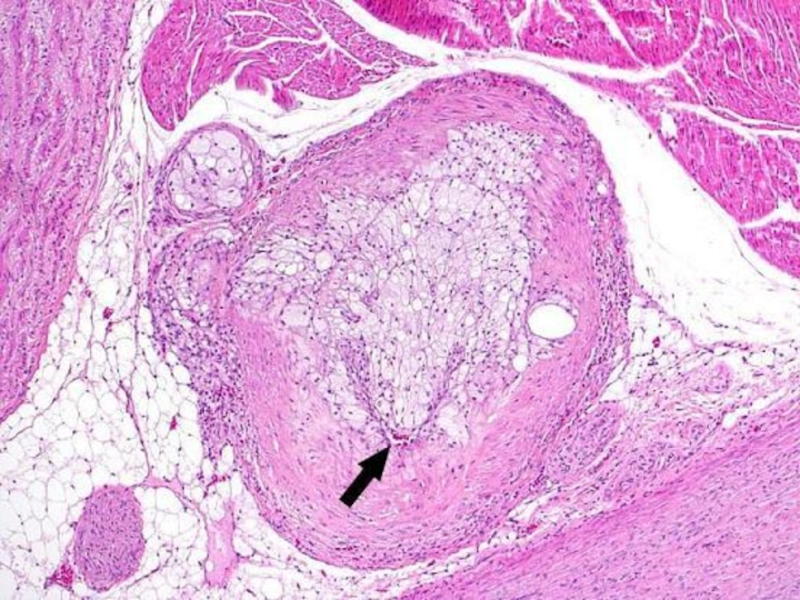

Слайд 15Stages of atherosclerosis (microscopic):

Prelipidic stage (macro: no changes, increase

of endothelium permeability)

Lipoidosis (lipids infiltrate the intima)

Liposclerosis (in the plaque

center – lipids and proteins, on the periphery– connective tissue and newly formed vessels)

Atheromatosis (lipoprotein detritus, fibers destruction, arrosion of plaque vessels tissue)

Atherocalcinosis (lime in the form of granules and plates of violet color when stained with hematoxylin/eosin)